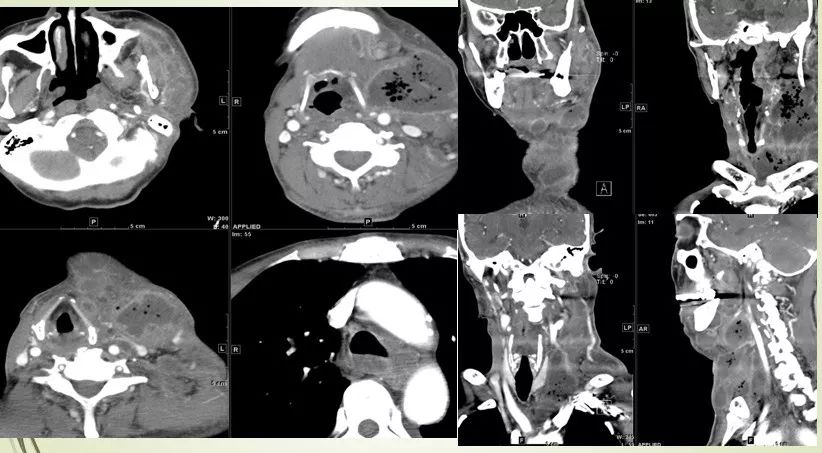

各间隙感染病例:

02 咀嚼肌间隙、翼下颌间隙、颊间隙

男,31岁,患者约3天前出现右侧面部口角区局限性肿胀,无明显触压痛,既往右侧下颌后牙区阵发性锐痛,曾自行口服消炎药处理,自诉牙痛症状无明显缓解,约3天前牙痛症状加重,伴夜间痛,后自觉右侧面部肿胀,约2天前开始发热,体温39.8℃。

03 眶下间隙、颊间隙、咀嚼肌间隙、翼颌间隙

男,41岁,4天前右上后牙疼痛,右侧面部肿胀3天余。

04 咀嚼肌间隙、颌下间隙、左侧颞下间隙,颊间隙,翼颌间隙

男,55岁,左下后牙反复肿疼1年余,加重1月余,疼痛剧烈伴张口受限,面部肿胀。

咀嚼肌间隙有脓肿形成。

05 颌下间隙、颏下间隙

女,68岁,10天前自觉右侧下颌后牙区间断性钝痛,6天前发现右侧颌下区及颏下区肿胀,伴明显触压痛。

龋齿并冠周炎,咽旁间隙有肿大淋巴结。

06 颌下间隙

64M,1个月前出现右下后牙钝痛伴咬合痛,自服红霉素,症状减轻。20天前发现患侧颌面及牙龈肿胀,伴有牙松动、牙周溢脓,抗炎效果不佳。约10天前曾行“脓肿切开引流”,#46、#47拔除。

骨髓炎并颌下间隙及下唇部感染。

07 颌下间隙、咽旁间隙

男,12岁,因“右面部肿痛2天。

淋巴结炎累及颌下间隙、咽旁间隙。

08 颈动脉间隙、咽后间隙、颌下间隙

右侧颈部肿物入院。

淋巴结结核累及咽后间隙。

15 多间隙受累

(1)左下后牙疼痛11天余,颈部肿胀10天。

(2)右侧颌面部弥漫性肿胀1月余。